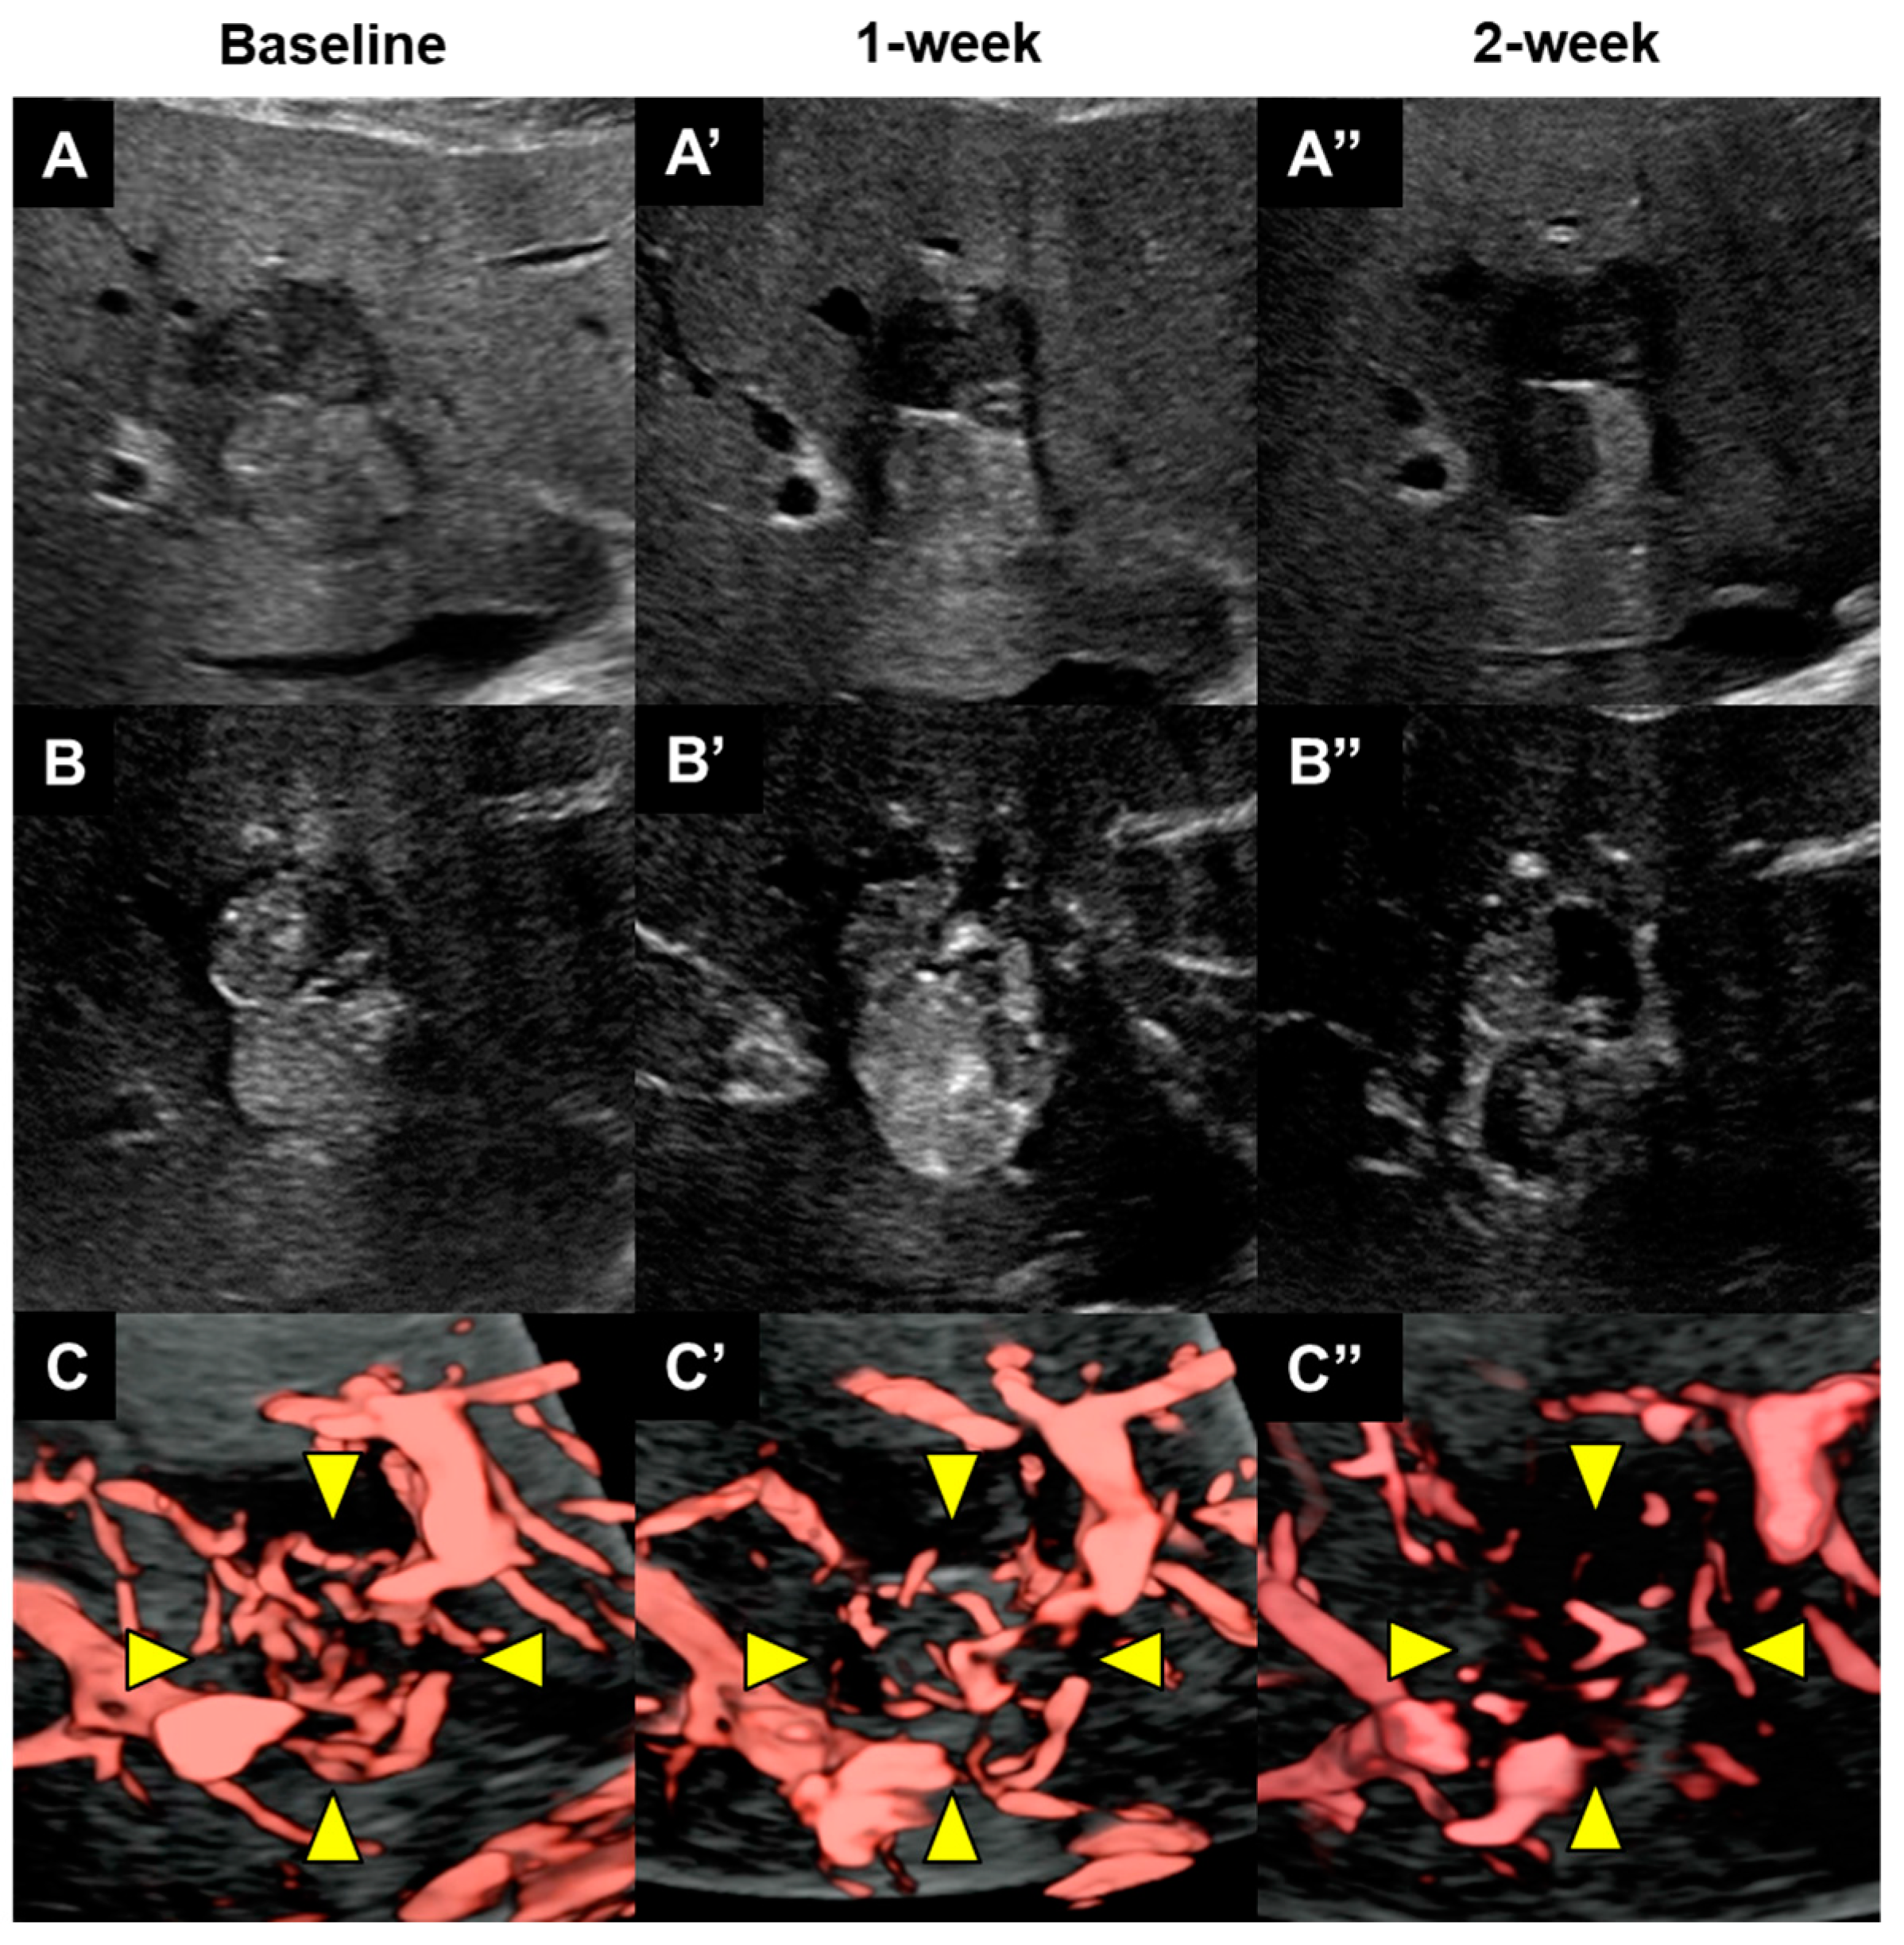

- Muraishi, N.; Kawamura, Y.; Akuta, N.; Shindoh, J.; Matsumura, M.; Okubo, S.; Fujiyama, S.; Hosaka, T.; Saitoh, S.; Sezaki, H.; et al. The Impact of Lenvatinib on Tumor Blood Vessel Shrinkage of Hepatocellular Carcinoma during Treatment: An Imaging-Based Analysis. Oncology 2023, 101, 134–144. [Google Scholar] [CrossRef]